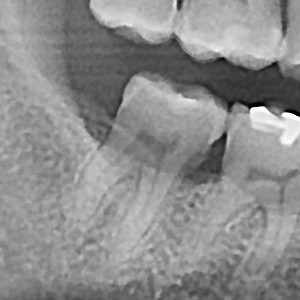

충치치료&신경치료 하루에 끝나는 신경치료